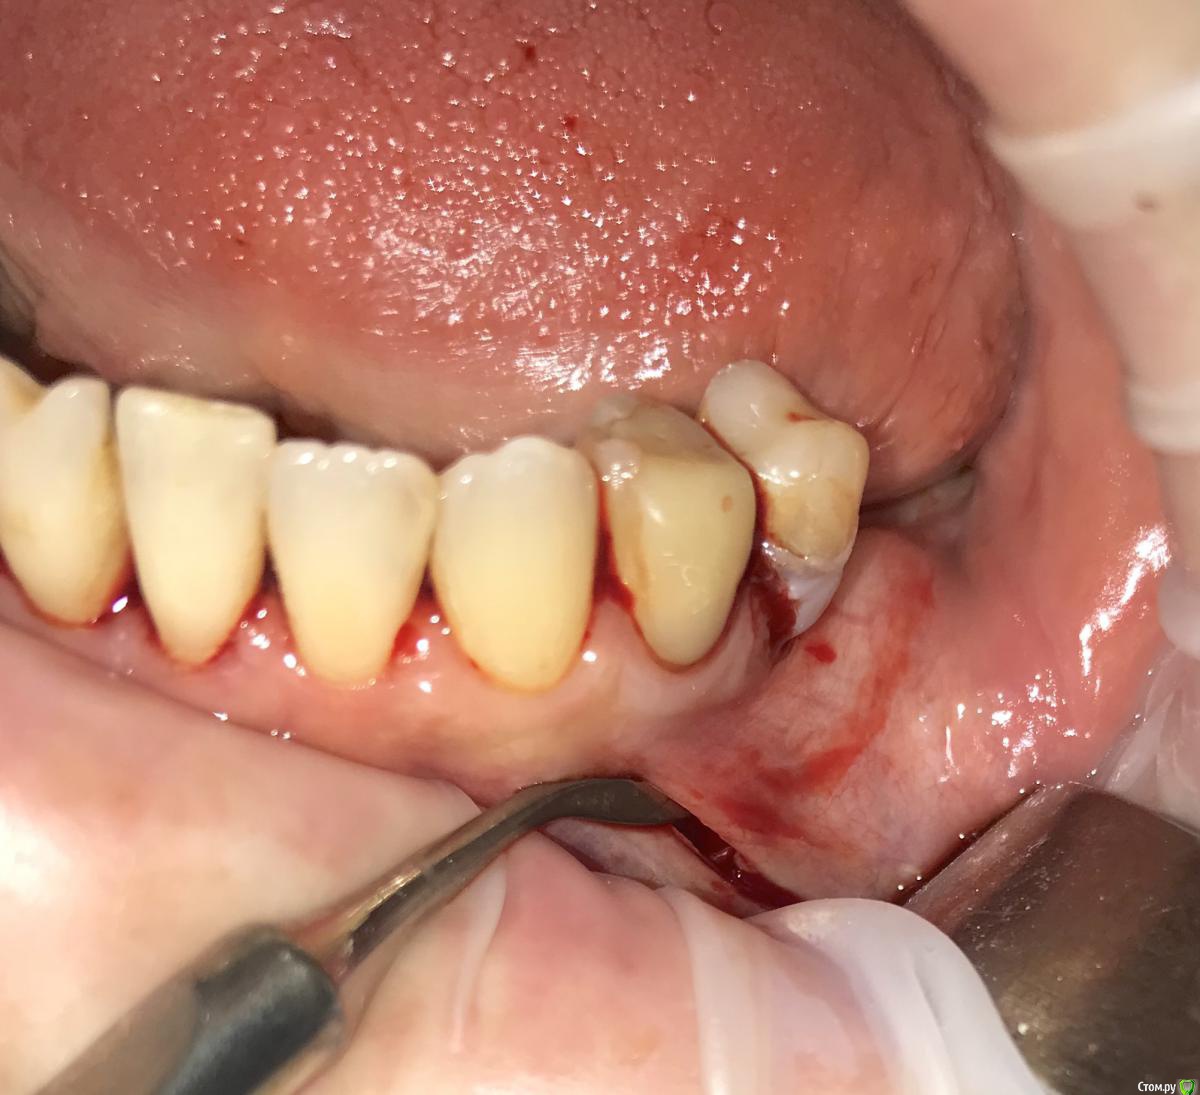

колесников Опубликовано 31 мая, 2019 Автор Поделиться Опубликовано 31 мая, 2019 Ещё случай.Через 3 мес ожидания 4 Ссылка на комментарий

колесников Опубликовано 8 июня, 2019 Автор Поделиться Опубликовано 8 июня, 2019 Спрашивали,что будет если графт не попал поднадкостнично. Аллографт за год лизируется полностью. Биотип улучшился,возможно произошло оздоровление пародонтоа в целом,но думаю это только результат усильной васкуляризации. Ксерографт ,вероятно, стал бы прободать наружу. 1 Ссылка на комментарий